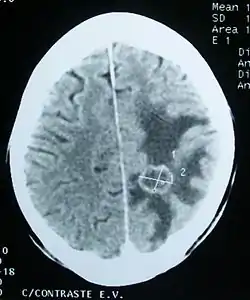

![]() استسقاء (المناطق الأغمق لونا) المحيطة بورم دماغي ثانوي. استسقاء (المناطق الأغمق لونا) المحيطة بورم دماغي ثانوي. | |